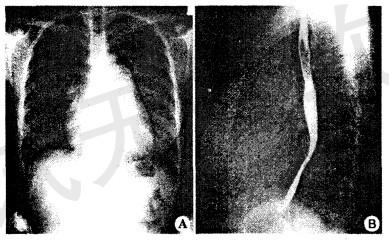

问题 女性,48岁。5年来渐进性劳累后心悸、气短,1年来加重,曾有夜间憋醒,需坐起后缓解,既往有关节痛史。检查发现心脏扩大,可闻及杂音,胸片显示如下。 按NYHA分级,该患者目前的心功能应是

解析 患者为中年女性,既往有关节炎史,体检心脏扩大,心脏有杂音,胸片心外形呈梨形,心脏左缘的肺动脉及左心房段突起,食管吞钡检 查显示明显左心房食管压迹,提示左心房扩大可能。全面分析患者的心脏病变为“风湿性心脏病,二尖瓣狭窄'故该患者最可能的心脏病变是风湿性心脏病。二尖瓣狭窄的典型杂音为心尖部舒张期隆隆样杂音。患者目前表现为劳累后气短,心功能应属NYHAII级。